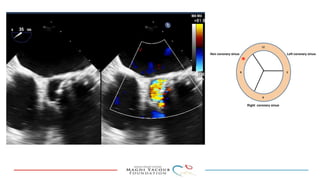

This document provides an overview of percutaneous prosthetic valve leakage (PVL) closure, including indications, approaches, techniques, and closure devices. It discusses that over 210,000 prosthetic valve surgeries are performed each year, with PVL occurring in some cases. While surgical closure has a high mortality rate, percutaneous closure has a procedural success rate of 86% and less complications. Indications for closure include symptomatic heart failure, hemolysis, rocking prosthesis, or leaks over 30% of the sewing ring. Techniques discussed include retrograde and transapical approaches using devices like the Amplatzer and Occlutech plugs. A team approach and techniques like sequential deployment are emphasized for